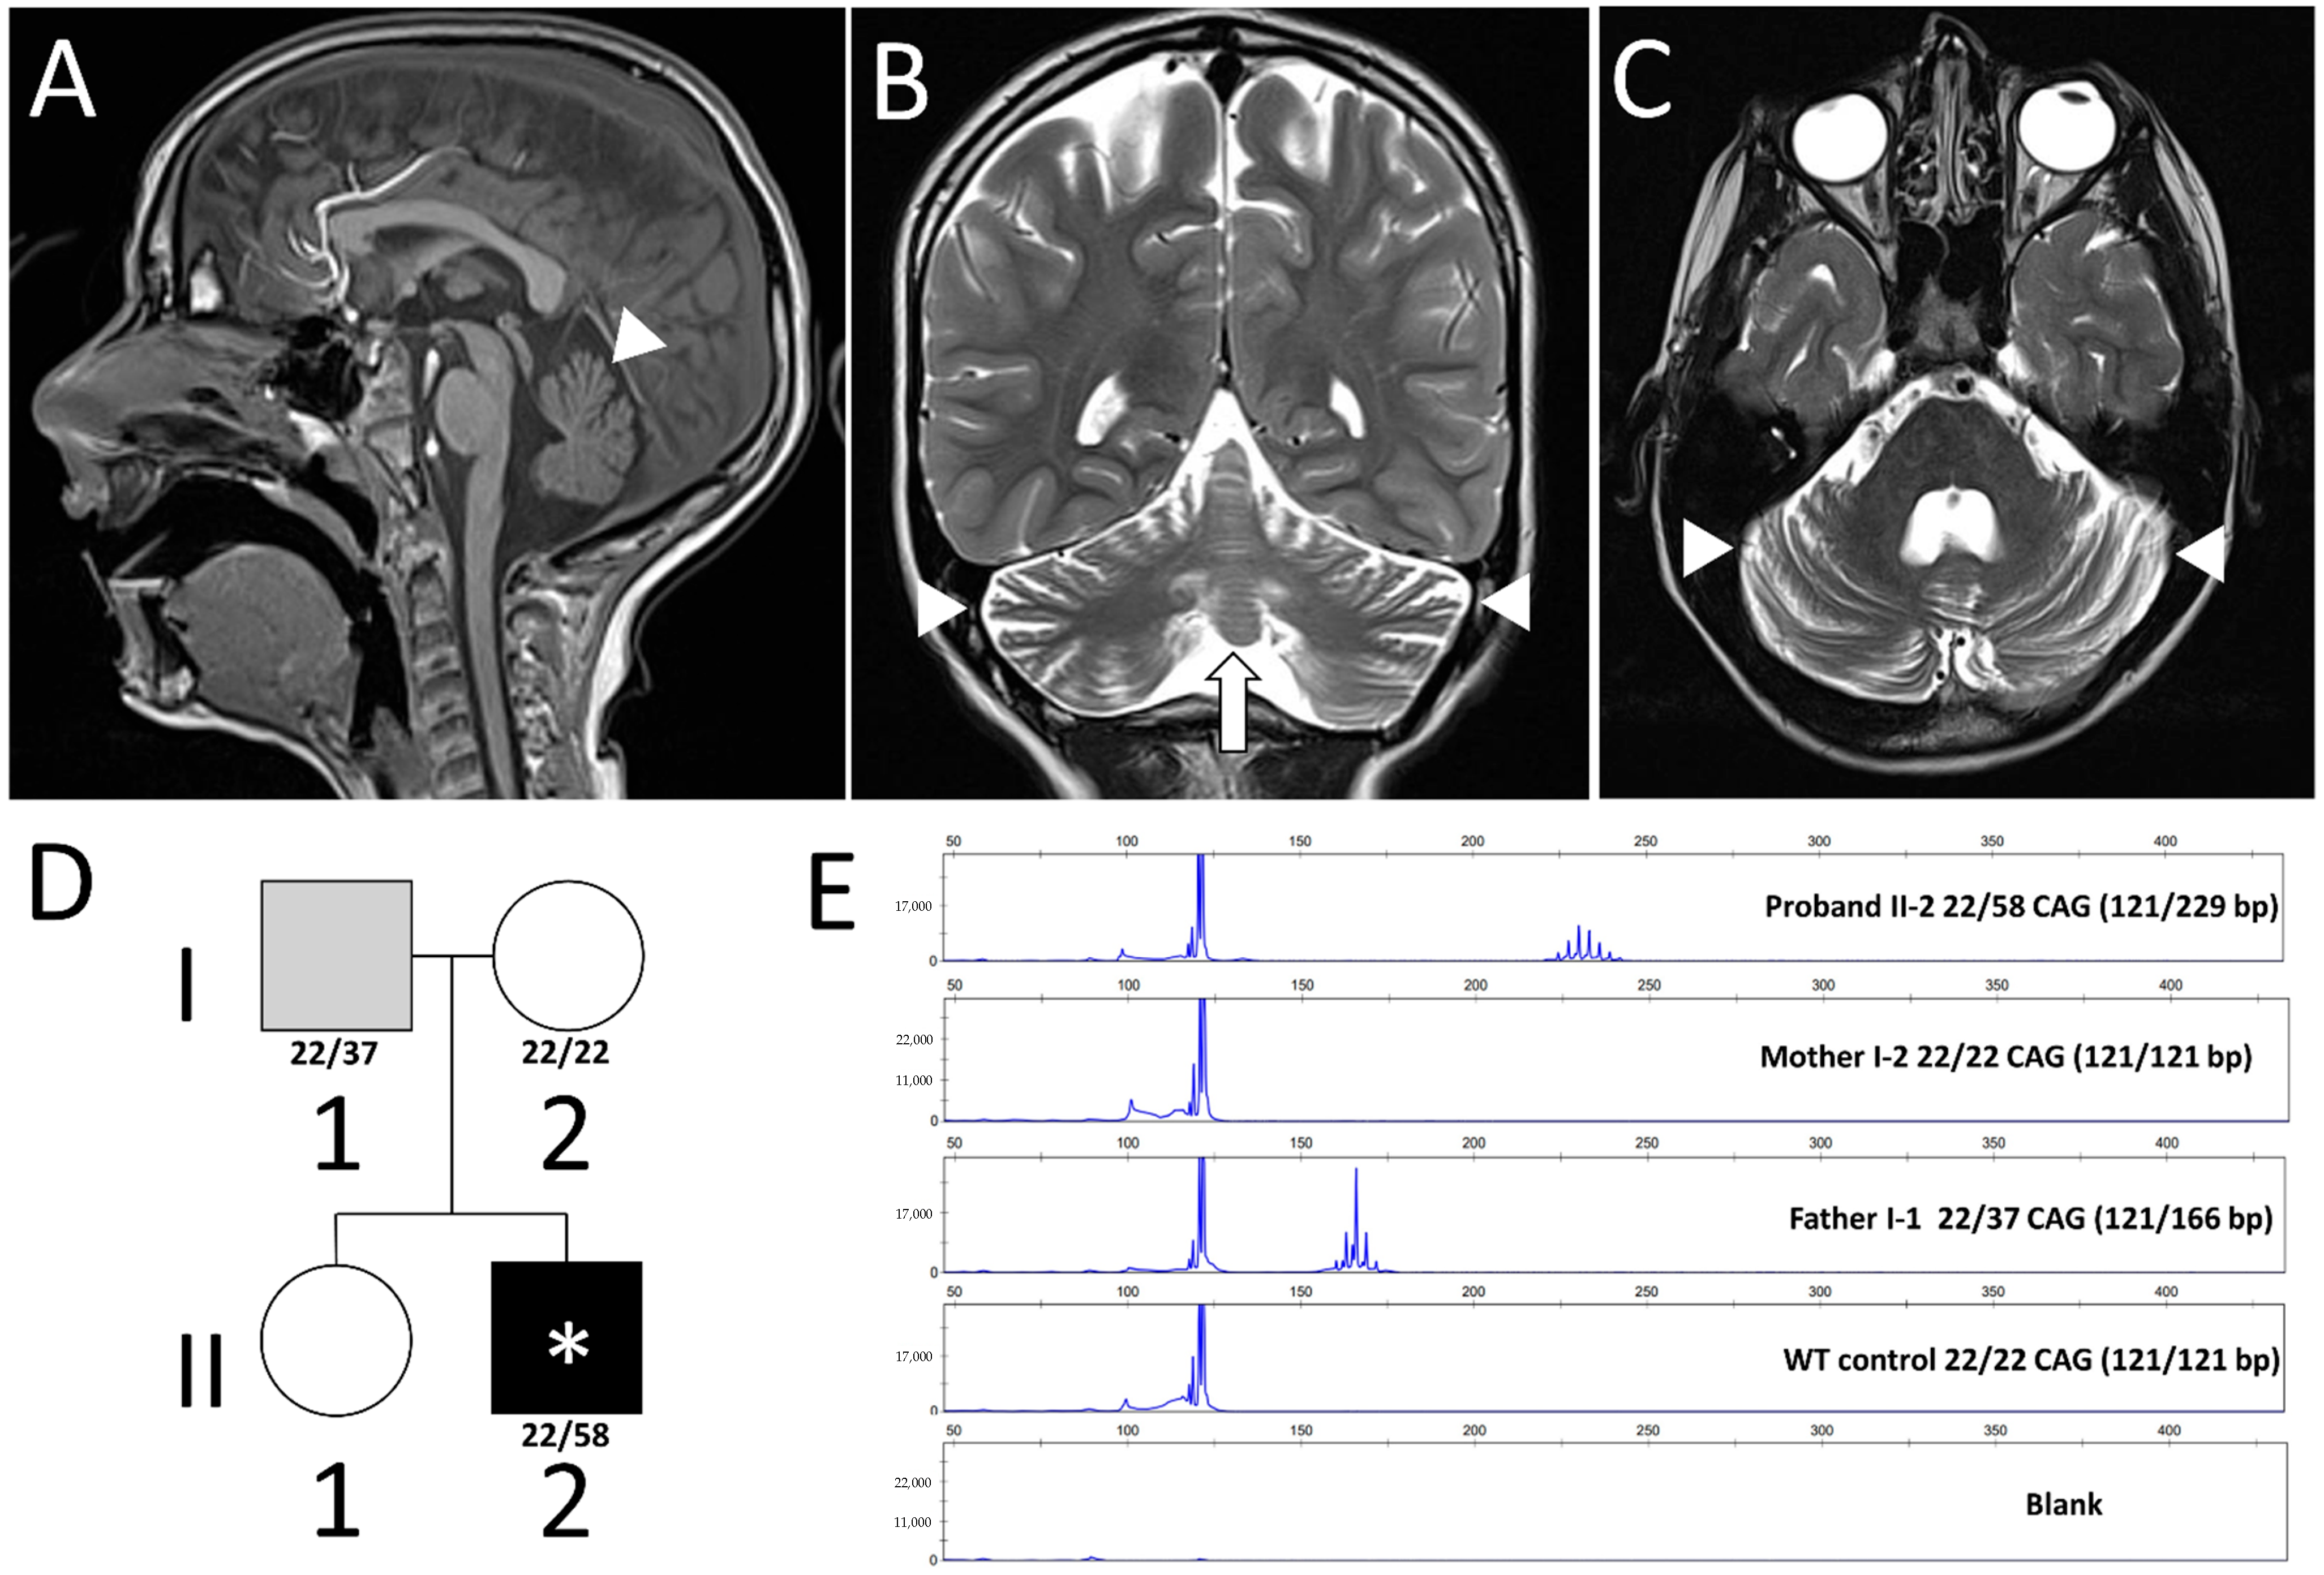

| Inheritance (allele) | Maternal (49) | Paternal (n/a) | Paternal (47) | Paternal (45) | Paternal (51) | Paternal (43) | Paternal (40) | Paternal (40) | Maternal (45) | Maternal (43) | Paternal (42) | Maternal (45) | Paternal (40) | Paternal (43) | Paternal (40) | Paternal (43) | Paternal (39) | Paternal (40) | n/a | Paternal (37) | Paternal (n/a) | Paternal (n/a) |

| Age of onset | neonatal | neonatal | 6 months | 6 months | 4 months | 2 months | infantile | 3 months | 3 months | 2 weeks | 6 months | 10 months | 3 months | 10 months | 11 months | neonatal | 2 years | 5 years | 2 months | 8 years | 6 years | 6 months |

| Signs or symptoms at onset | Nystagmus, dysphagia | Hypotonia, dysphagia | Hypotonia, developmental regression | Hypotonia, eye movement abnormalities, myoclonus | Developmental delay, hypotonia, dyskinesia | Hypotonia | Developmental delay, microcephaly | Developmental regression | Focal seizures | Apnea episodes | Hypotonia | Hypotonia, developmental delay | Hypotonia, seizures | Hypotonia, developmental delay | Hypotonia, developmental delay | Hypotonia, apnoea episodes | Ataxia, progressive movement disorder | Ataxia, developmental delay | Eye movement abnormalities | Learning disability, cerebellar ataxia | Limb tremor | Febrile seizures, mild developmental delay |